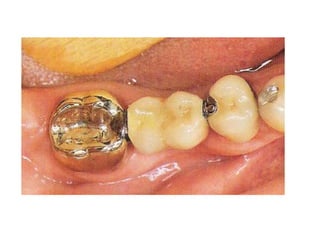

*full veneer metal

crown: it is a full

metal cast crown

that covers all the

coronal tooth

surface.